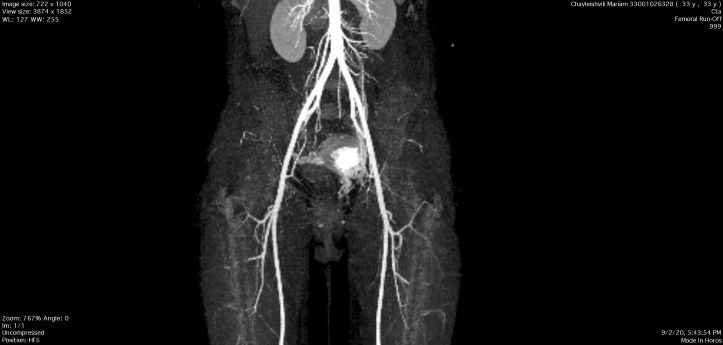

პაციენტს ჩაუტარდა მენჯის სელექტიური სუბტრაქციული ანგიოგრაფია და საშვილოსნოს არტერიის ანევრიზმის ტრანსკათეტერული არტერიული ემბოლიზაცია, რომელიც ენდოვასკულური მკურნალობის ოქროს სტანდარტია, რადგან ის არაინვაზიური, უსაფრთხო და მეტად ეფექტურია.

ოპერაციისშემდგომი მდგომარეობის შეფასების მიზნით და სისხლძარღვების სრული ოკლუზიის გამოსარიცხად პაციენტს ჩაუტარდა ემბოლიზაციის შემდგომი ანგიოგრაფიული და კომპიუტერული კვლევა, ადრეულ პოსტოპერაციულ პერიოდში და ოპერაციიდან 2 თვეში, რის შედეგადაც, პათოლოგია აღარ გამოვლინდა.